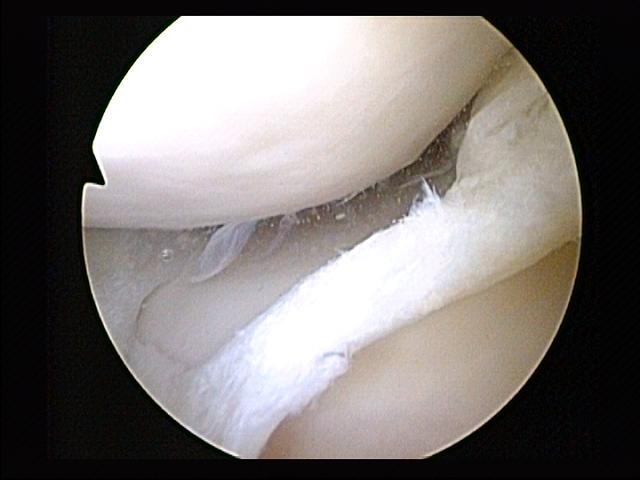

Knee with complete ACL rupture showing torn ligament, bone bruises on lateral femoral condyle and posterolateral...

Knee with medial meniscus tear (bucket-handle type) showing displaced meniscal fragment, joint effusion, and...